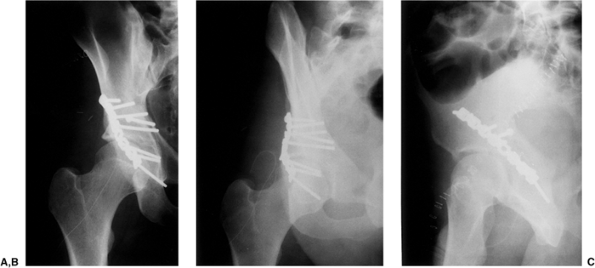

|

Figure 41.46. A–C.

AP and 45-degree oblique x-rays. These x-rays and the figures that follow are from the same patient whose surgery supplied the foregoing intraoperative photographs used to demonstrate the Kocher-Langenbeck approach. |

accident, sustaining an atypical T-shaped fracture of the acetabulum

with intra-articular comminution (Figs. 41.46, 41.47 and 41.48).

ORIF was advised because of the instability and incongruency of the hip

joint. Surgery was performed 4 days after injury by using the

Kocher-Langenbeck approach (Figs. 41.49, 41.50, 41.51 and 41.52).

One week later, the patient was discharged to home from the hospital

with instruction to proceed with toe-touch weight bearing with crutches.

Figure 41.50. A–C. Postoperative x-rays.